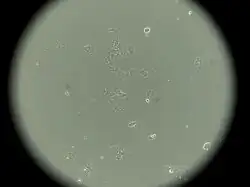

Characteristics of MCF-7 cells

MCF-7 cells have the following characteristics:[2][5][6][7][8][9]

- Primary tumor (invasive breast ductal carcinoma)

- Originate from pleural effusion

- Estrogen receptors present[10]

- Proliferative response to estrogens

- Presence of progesterone receptors

- Cannot have ERBB2 gene amplification (with Her2/neu protein overexpression)

- Tumorigenic in mice but only with estrogen supplementation if engrafted into the subcutaneous fat or mammary fat pad

- Tumorigenic in mice without estrogen supplementation if engrafted intraductally[11]

- Luminal epithelial phenotype

This cell line retained several characteristics of differentiated mammary epithelium, including the ability to process estradiol via cytoplasmic estrogen receptors and the capability of forming domes.